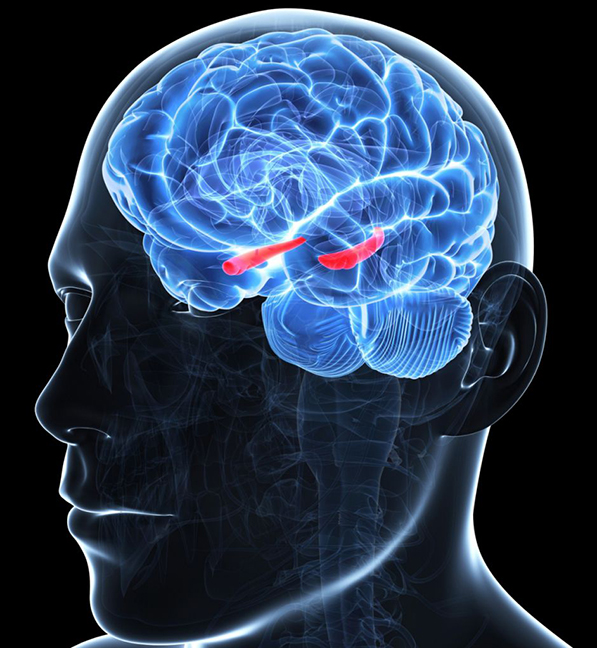

NEUROLOGIJA

Vitamin D i zdravlje mozga

Jedno istraživanje obavljeno na Univerzitetu u Kvinslendu, Australija, objašnjava zašto je vitamin D od vitalnog značaja za zdravlje mozga i na koji način njegov nedostatak dovodi do poremećaja kao što su depresija i šizofrenija. Istraživači su otkrili da nivoi vitamina D utiču na neku vrstu "građevinskih skela" u mozgu, nazvanih perineuronske mreže.